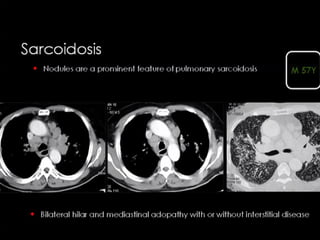

Sarcoidosis

The majority of nodules located

along the bronchovascular bundle

(yellow arrow).

Perilymphatic and Random distribution of

nodules , seen in sarcoidosis.